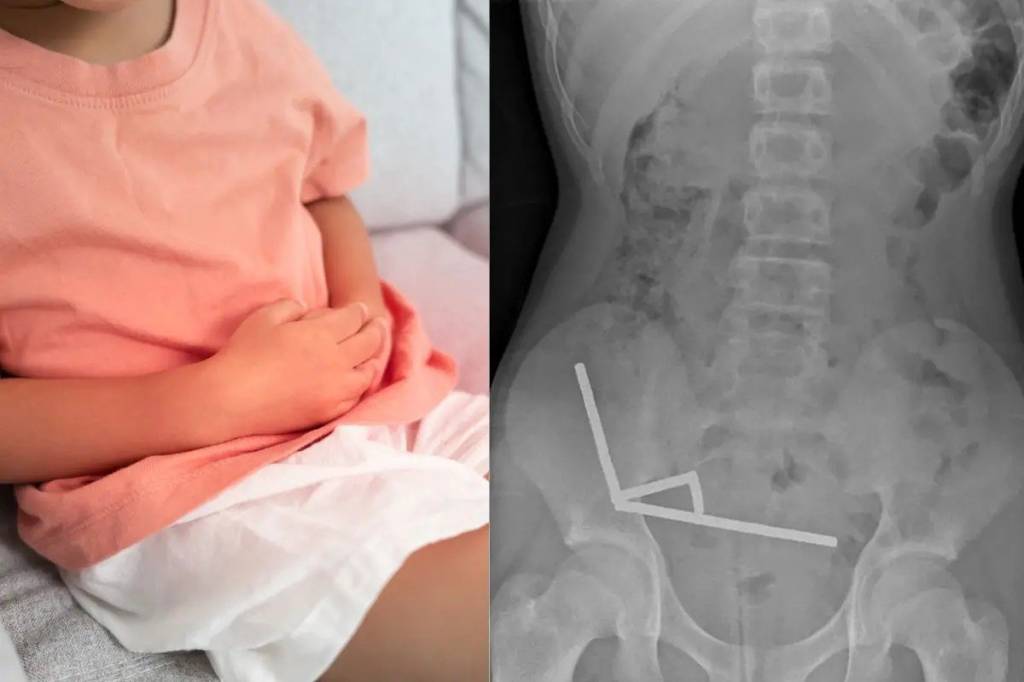

Avvaliga, bemorda qorin og‘rig‘i kuzatilgach, oradan bir hafta o‘tgach shifokorga murojaat qilgan. Kompyuter tomografiyasi magnitlar ichak ichida to‘rtta zanjir holida yopishib qolganini ko‘rsatgan.

Operatsiya vaqtida magnitlar bosimi tufayli ichak devorlarida nekroz va yirtilish boshlangani aniqlangan. Magnitlar olib tashlangan, biroq bola ichagining bir qismi kesib olingan.